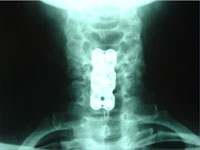

- Case Report: Cervical Spine Post-Surgery

Probably no area of chiropractic spinal manipulation is as challenged as treating the post-surgical patient who is the same, worse, or disenchanted with their surgical outcome. Certainly, the opportunity to treat the patient before surgical intervention is best. When confronted with this post-surgical patient, however, the chiropractic physician proceeds as if with a patient who has not had surgery. i.e. The chiropractor will proceed with the careful history and clinical examination to determine what is causing the pain. That cause may be within the surgical site or adjacent to it. In treating the post-surgical spine, fusion or no fusion is a dictator of care. If there is a fusion, spinal manipulation is given to adjacent levels of the spine to the fused area. If there is no fusion, the doctor carefully proceeds as if no surgery. Some motion may be possible within the spine depending on the surgical procedure performed. (11)

Let’s look at some factors of interest and importance to a patient seeking chiropractic care for their post-surgical spinal problem. (11)